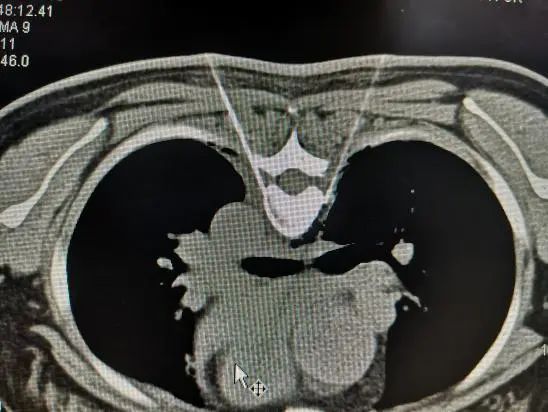

其实这项治疗叫做胸交感神经微创介入治疗,它是在影像学(X线、CT)引导下,采用微创经皮穿刺方式,应用神经阻滞剂或神经毁损药物以及射频消融等方法,对胸交感神经节进行阻滞或破坏,达到微创下胸交感神经节切除的目的。

胸交感神经被阻断后,它支配的上肢血管扩张,能起到改善局部血液循环和营养供应、消除异感、减轻疼痛的作用。胸交感神经微创治疗在影像引导下可以做到非常精准化,可取得与手术切除胸交感神经节相类似的效果,但治疗创伤小,风险明显减少。